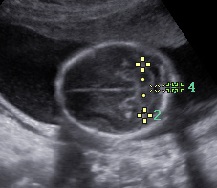

Cráneo

La determinación de la normalidad anatómica depende de la etapa del desarrollo en la que se pretende estudiar en contenido encefálico y del momento de aparición de las anomalías posibles; además, a diferencia de otros órganos cuya estructura madura es bastante estable y resistente a agresiones durante el embarazo, el contenido craneal puede verse afectado en cualquier etapa del embarazo, durante el nacimiento y en vida posnatal.

Las estructuras intracraneales después de la semana 18-20 del embarazo son muy características y permanecen visualmente invariables hasta el final del embarazo, solo modificando sus tamaños a medida que el feto crece. Esto es de gran ayuda ya que permite determinar la aparición de cambios que podrían sugerir desviación de la normalidad y aparición de una malformación congénita o lesión adquirida por eventos externos especialmente relacionados a infecciones y accidentes vasculares fetales.